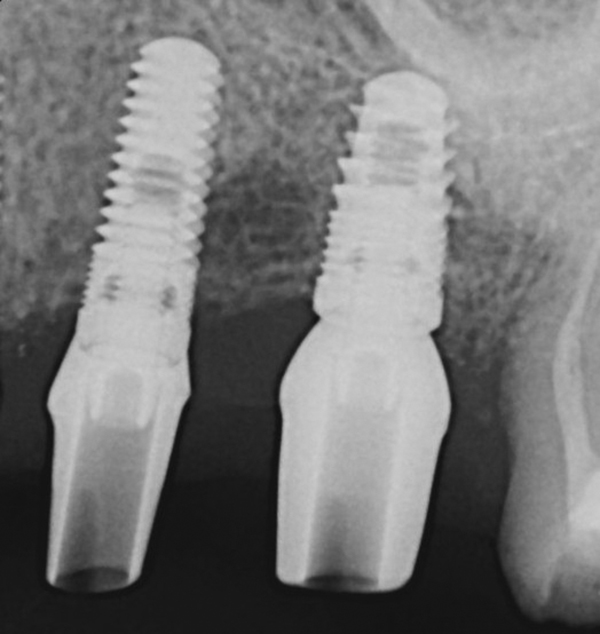

Fig 5. Radiograph of the implant at site No. 28 (shown in Figure 4) with an oversized cover screw, which was used to assist in stabilizing the implant within the osteotomy.

Figure 5

Apparently with time, stable implants placed with low initial torque develop bone characteristics around them that are similar to sites where implants were placed with a high initial torque (Figure 4 and Figure 5). Conversely, for implants placed with a high initial torque, the healing process, despite the high initial torque, provides a level of biologic stability that is not necessarily influenced by the initial insertion torque value.